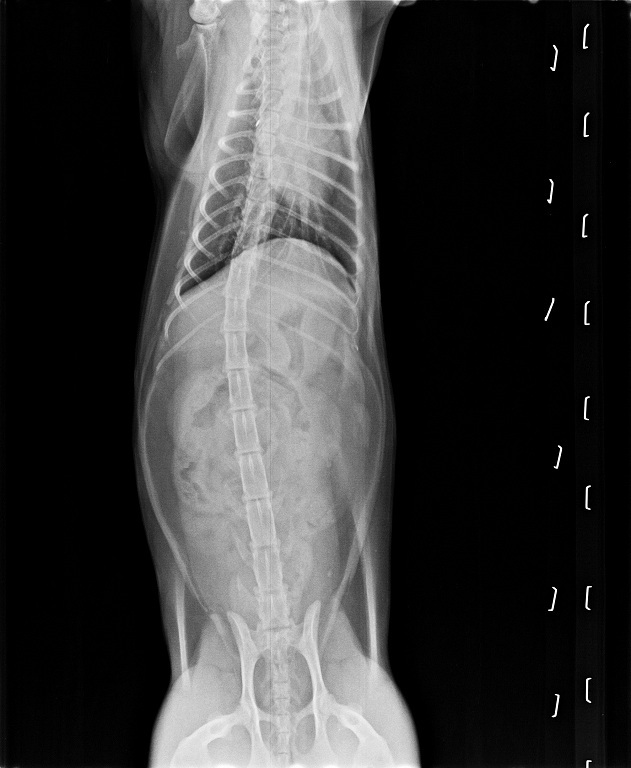

香香在醫院除了做詳細的血液檢查,

也拍了X光照片看清楚香香體內是否有吞入異物,

所幸X光照片並沒有拍到有吞入異物的跡象。